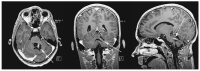

Abbildung 2: Initiale Magnetresonanzangiographie (MRA): Hinweis auf eine arteriovenöse Malformation (AVM) der Arteria cerebelli superior links.

MRA

Abbildung 6: Magnetresonanztomographie-(MRT-) Kontrolle nach 6 Monaten: Nach Blutungsresorption arteriovenöse Malformation (AVM) sichtbar

MRT